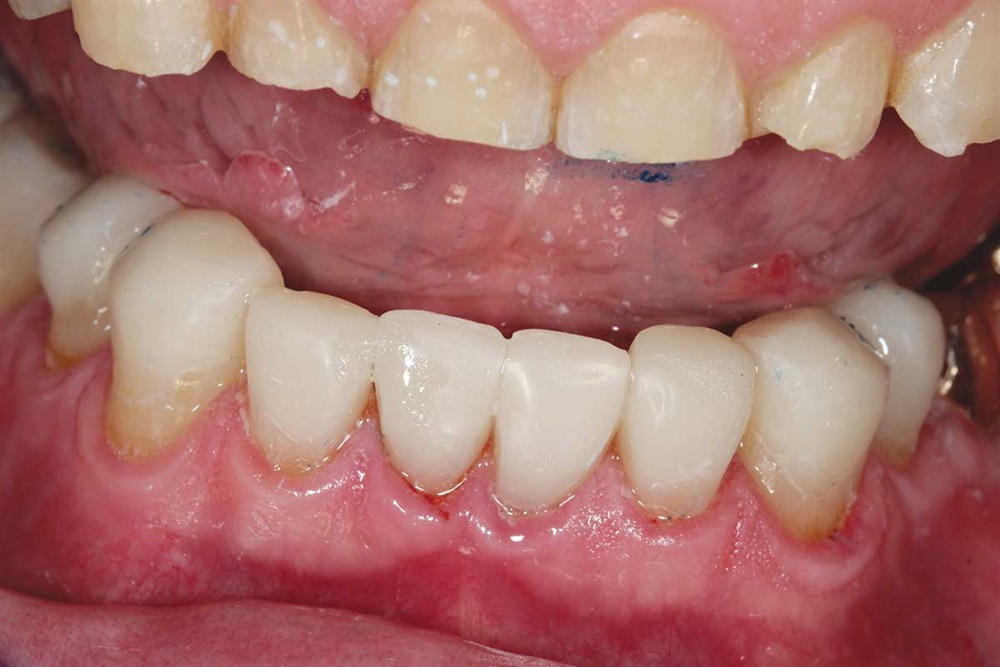

Fig. 14–16: It is hard to see, but the patient’s bicuspids nearly miss in occlusion because the upper bicuspids are buccal to his lower bicuspid. One reason for ortho would have been to expand the lower arch to get more occlusion on the bicuspids.

Fig. 15

Fig. 16